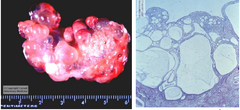

amyloidosis (congo red stain)

what is this extracellular accumulation?